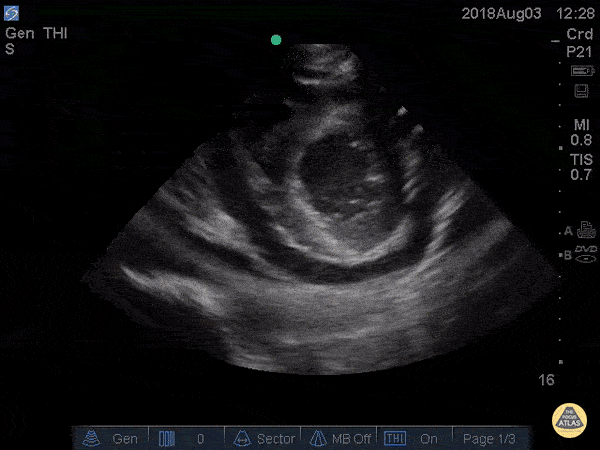

The PLAX view is versatile and allows the recognition of multiple landmarks, making it good for visual estimation of LV contractility. It is essential to optimize the view ensuring a true sagittal long axis, as being oblique to the LV chamber may underestimate its size and overestimate its emptying. The PSAX view at the level of the papillary muscles reveals the entire muscular circumference and concentric squeeze of the LV. It is useful to estimate both global function and focal wall motion abnormalities. The A4C view, although technically challenging, provides good insight into the global myocardial function and chamber size.

LV CONTRACTILITY

Qualitative assessment of the LV and visual estimation of Ejection Fraction is based on three parameters:

Endocardial excursion.

Myocardial thickening.

Movement of the anterior leaflet of the mitral valve.

A qualitative assessment is typically categorised as:

Normal (LVEF 50-65%)

Moderately Depressed (LVEF 30-50%)

Severely Depressed (LVEF < 30%)

Hyperdynamic (LVEF > 65%)

SIGNIFICANTLY IMPAIRED / DILATED LV

A severely depressed LV contractility, particularly when paired with a plethoric IVC or lung B-lines, indicates systolic heart failure. Chronically raised afterload can lead to severe dilation of the LV.